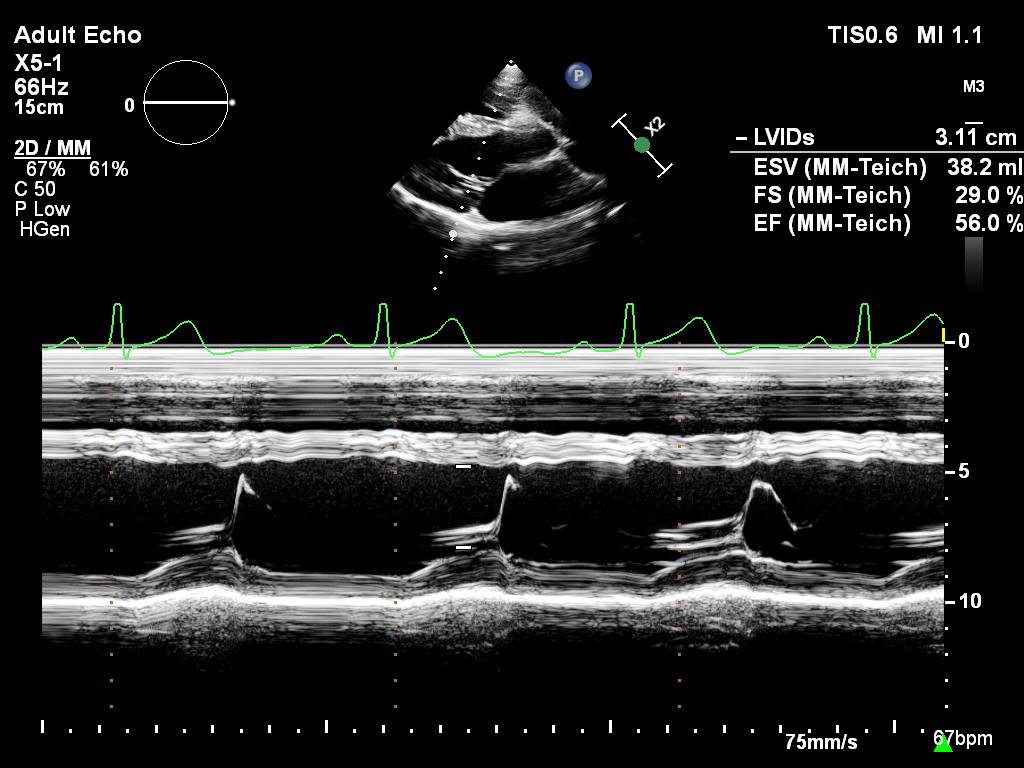

M 型Teichholtz法

测 量方法:在二维超声心动图的指导下,选择胸骨旁左心长轴切面,使二尖瓣前叶与声束垂直,其取样线通过二尖瓣瓣尖水平,测量左室的收缩末径和舒张末径,计算出左室的射血分数。

计 算公式:M型超声心动图测量收缩功能是对左室腔进行几何形态的假设,其中长椭球形是最常用的几何假设。然后通过Teichholtz公式计算左室的容量。由此可见,M超是测量二维的径线,建立数学模型,通过Teichholtz公式估算出的左室容积。M超的优点是简单易行,已沿用多年,对形态正常的心室还是比较准确的。但是对形态异常,超出正常大小,或有室壁运动异常的心脏,测量值可能有较大的误差。超声的ASE指南已不再推荐这种方法。